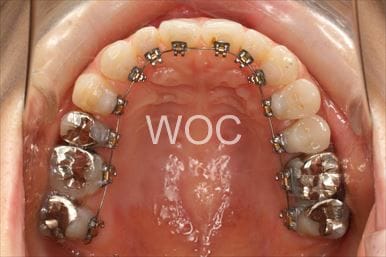

開咬開咬

上下舌側矯正を希望。上顎両側第一小臼歯の抜歯としたが上顎右側第二小臼歯は治療した歯であったため、抜歯部位を変更。治療の難度が上がったため治療期間が少し延長しました。

- 年齢:33歳女性

- 主訴:出っ歯、前歯で噛めない

- 基本矯正料金:1,295,000円

- 治療期間:2年8ヶ月

- 抜歯部位:上顎右側第二小臼歯、左側第一小臼歯